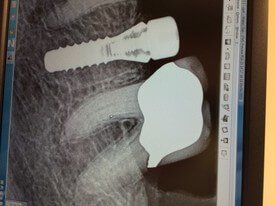

- It acts as an artificial root, usually made of titanium, that is surgically placed into the jawbone to replace the root of the natural tooth.

An immediate dental implant, or Teeth in a Day®, is placed in the jawbone immediately after a single tooth (or teeth) extraction. It is usually placed in the same visit as the extraction but can be done after two weeks and still qualify as an immediate dental implant.

This safe and effective treatment for replacing missing teeth is a good option if you have enough natural bone and an implant secure enough to support immediate placement and pressure on the new tooth.